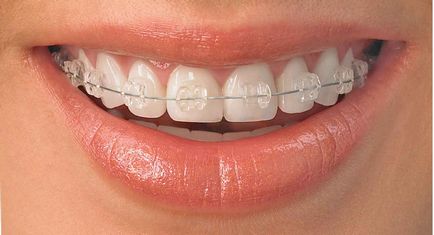

Ez egy külön zár minden fog (zárójelek), és az ív, amelyet bevittek mindegyik konzol, és így összeköti az összes fogat egyetlen lánc. A rendszer befolyásolja a foghelyzetei útján változások csont és a fogak feszültség vezetékek.

Ez ív kioldójának fog szállításáról és ellenőrzéséről helyzetük három síkban. Bármi rendszer álltál - Incognito láthatatlan fogszabályozó. nyelvi fogszabályozó. köztük nyelvi melles stb - ez vonatkozik minden tervez.